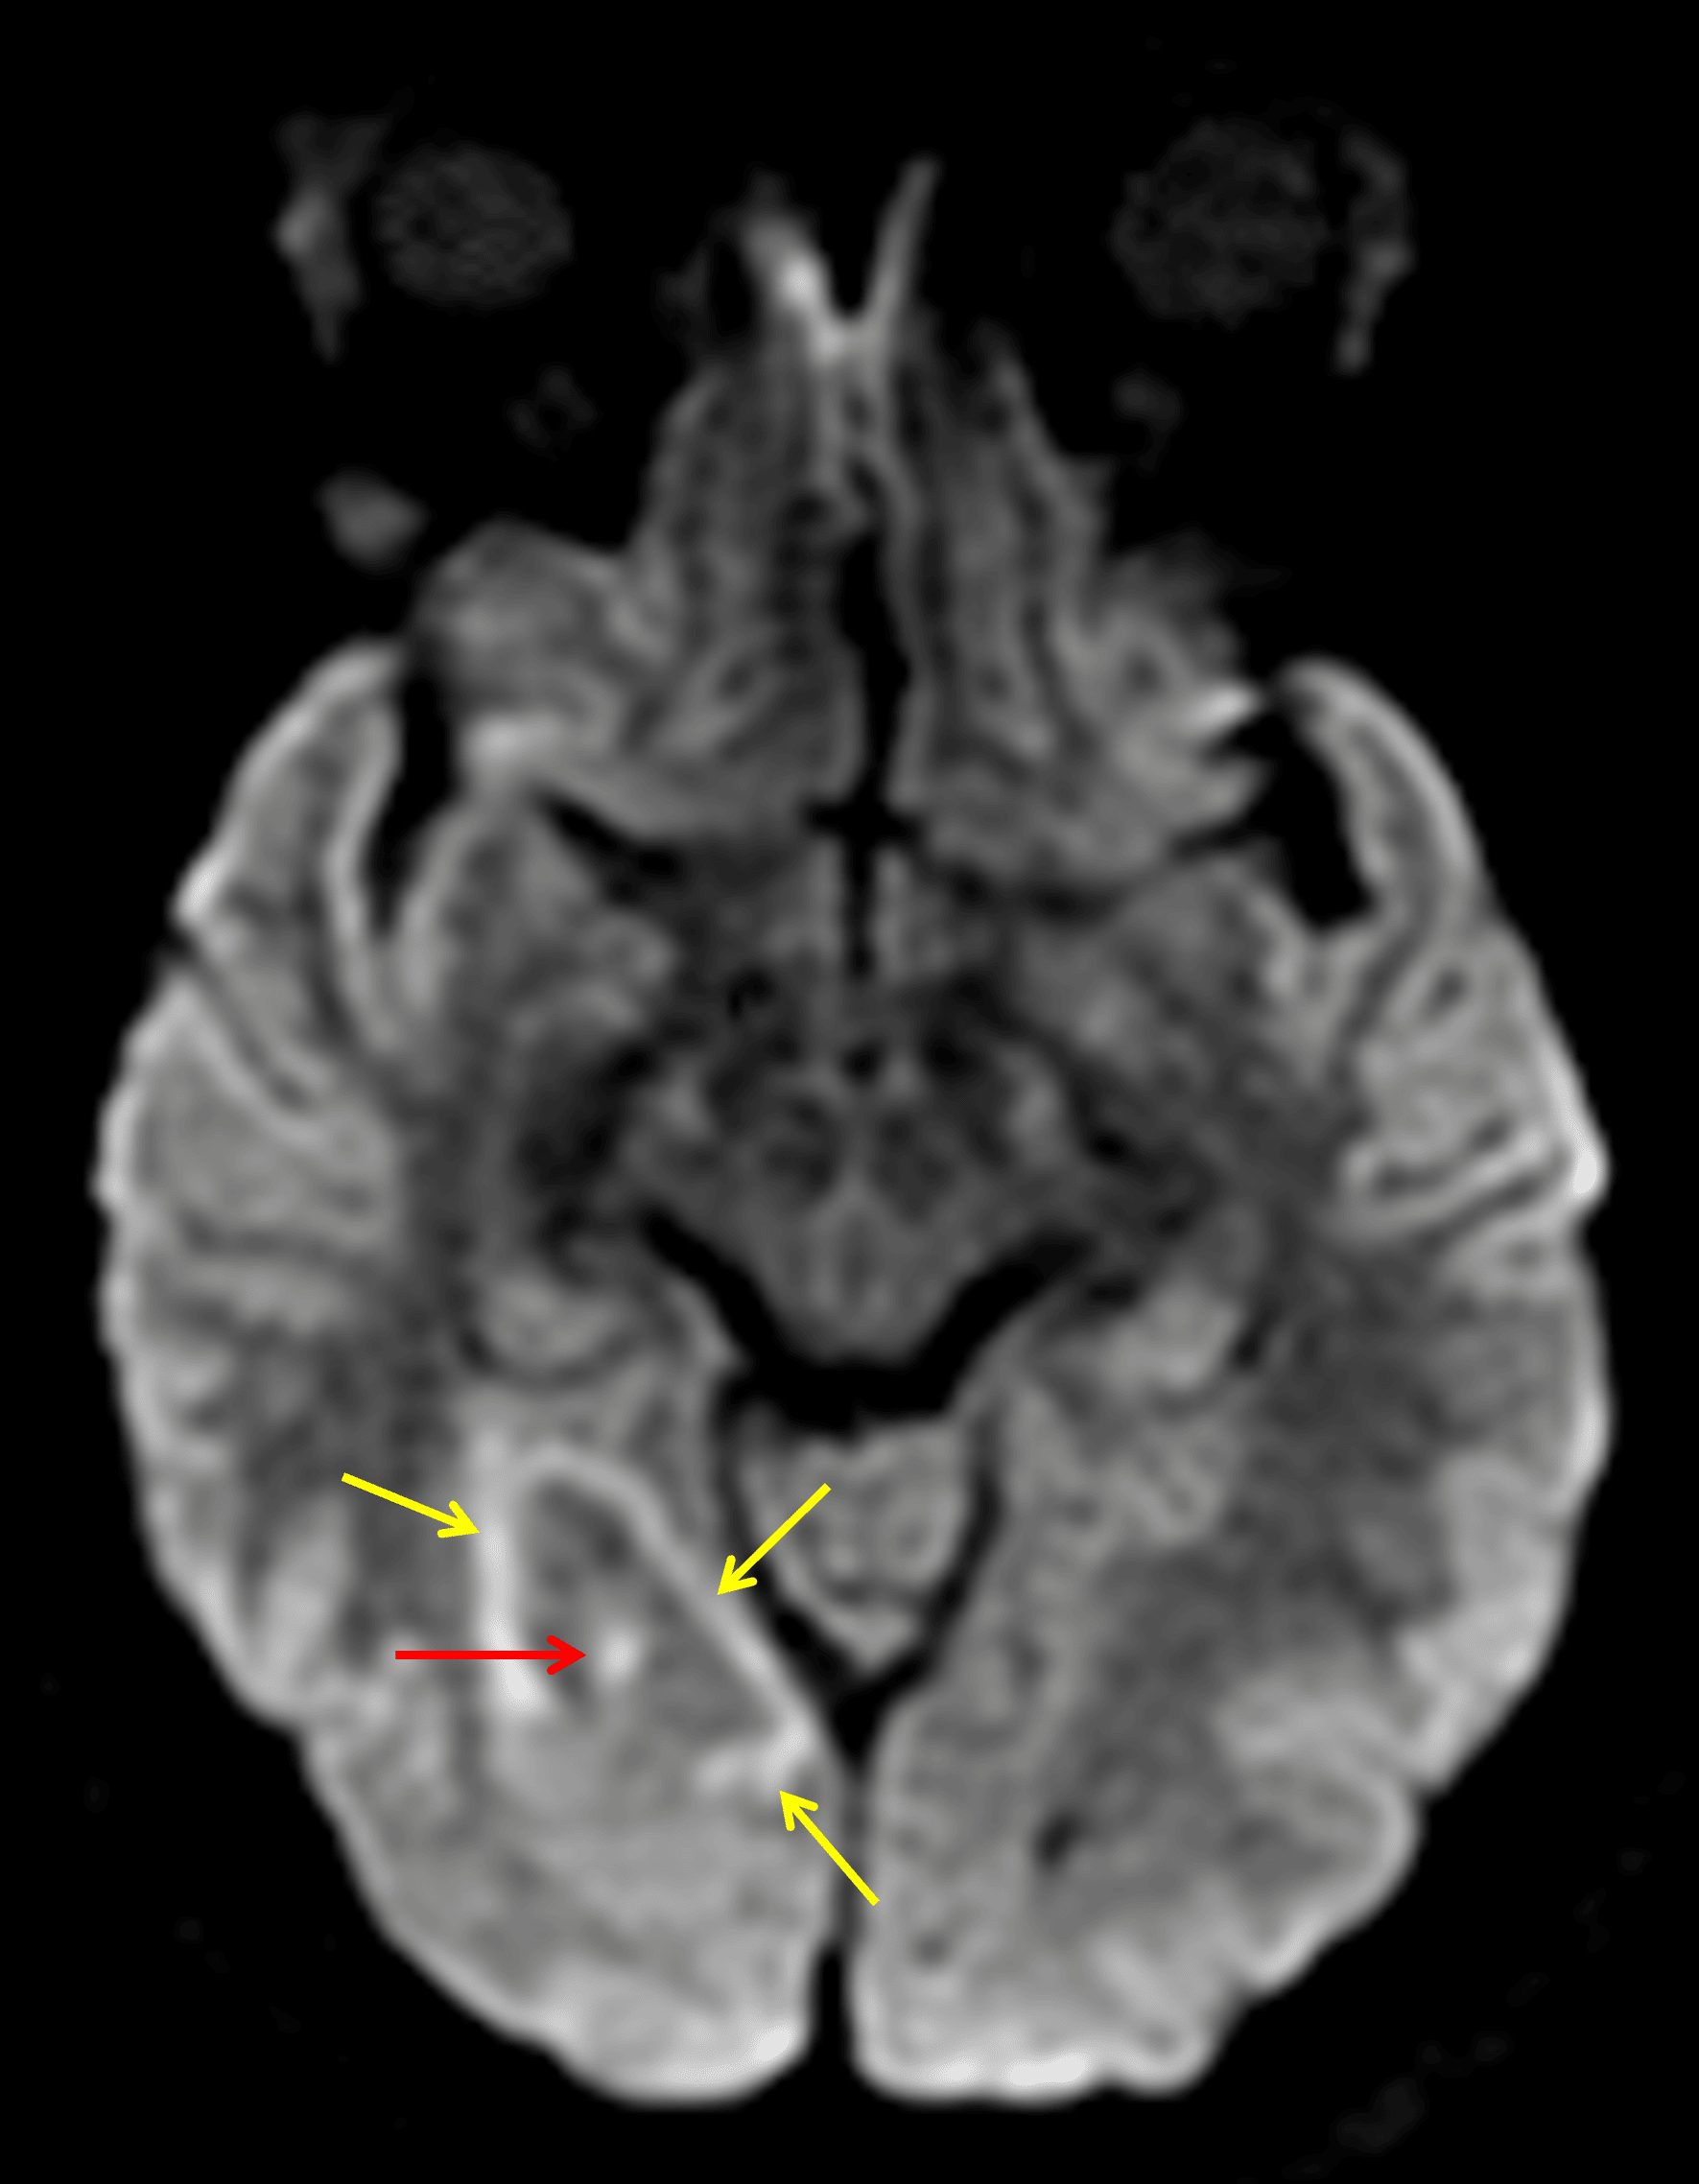

• Peripherally-enhancing lesion in the right occipital lobe measuring 1.7 x 1.3 x 1 cm with surrounding vasogenic edema and minimal local mass effect

Peripherally-enhancing lesion in the right occipital lobe (red arrow) with surrounding vasogenic edema.